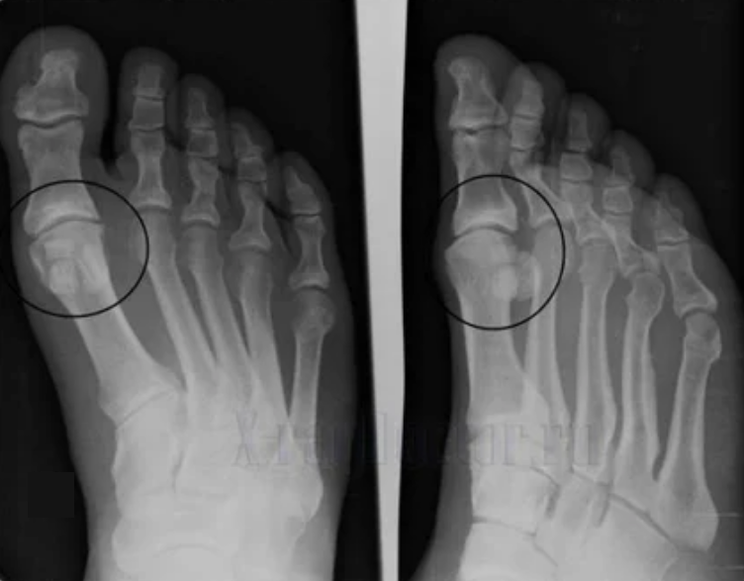

For diagnosis, rheumatoid doctors studied patient complaints and prescribed X -Ray examination.Usually, X -ray is used in 2 projections.The doctor looks at the presence of nourishing disorders in Hyaline cartilage and joints.If the joint distance is reduced, the bone is deformed or flattened, there is a follicle formation on the surface of the cartilage, osteoporosis is a clear sign of Arthrosis.During the test, arthritis shows the unstable joints: the axis of the limbs and subluxation are disturbed.

Usually a X -Ray picture cannot provide adequate information about the condition of the joint.For a more thorough study, the computerized tomography is prescribed, it is effective for bone testing.MRI is often used to study soft tissues.